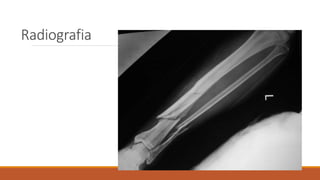

Radiografia

Organismo apresenta várias densidades aos

Densidade óssea: ossos absorvem mais

radiação que as partes moles, aparecem

BRANCOS.

Densidade de partes moles: menos que o

osso e mais que o ar (coração, músculos,

etc).

A imagem radiográfica aparece

quando há diferença de densidade

radiológica entre as estruturas

vizinhas do organismo.

Exemplo: na radiografia do tórax

aparecem ar (campos pulmonares),

partes moles e osso de maneira

distinta.